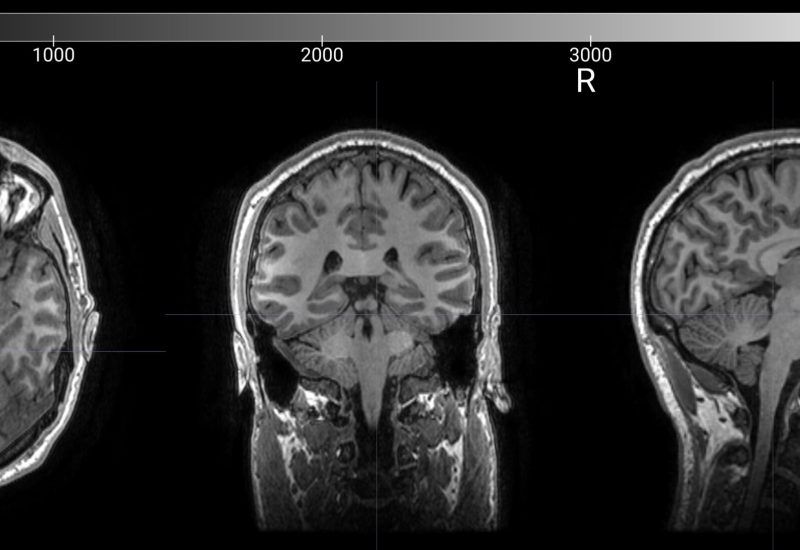

We use a 5 min structural MRI to increase the accuracy of your neuro-navigated TMS treatment.

Magnetic Resonance Imaging (MRI)